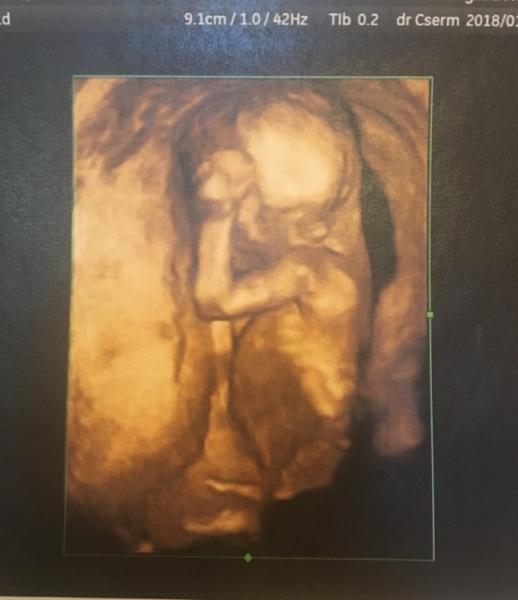

War gestern beim FA für ein check up.

Wollte das Geschleckt rausfinden aber mein Schatz wollte überhaupt kein Photoshooting

Aber sonst alles prima

Hallo alida das bild ist schön geworden und das hat meine erste ss das kind och gemacht nur mit der Hand mitten ins gesicht gelegt

Was ein schönes Bild < 3

Hat sich richtig versteckt, so nach dem Motto, ihr sieht mich nicht